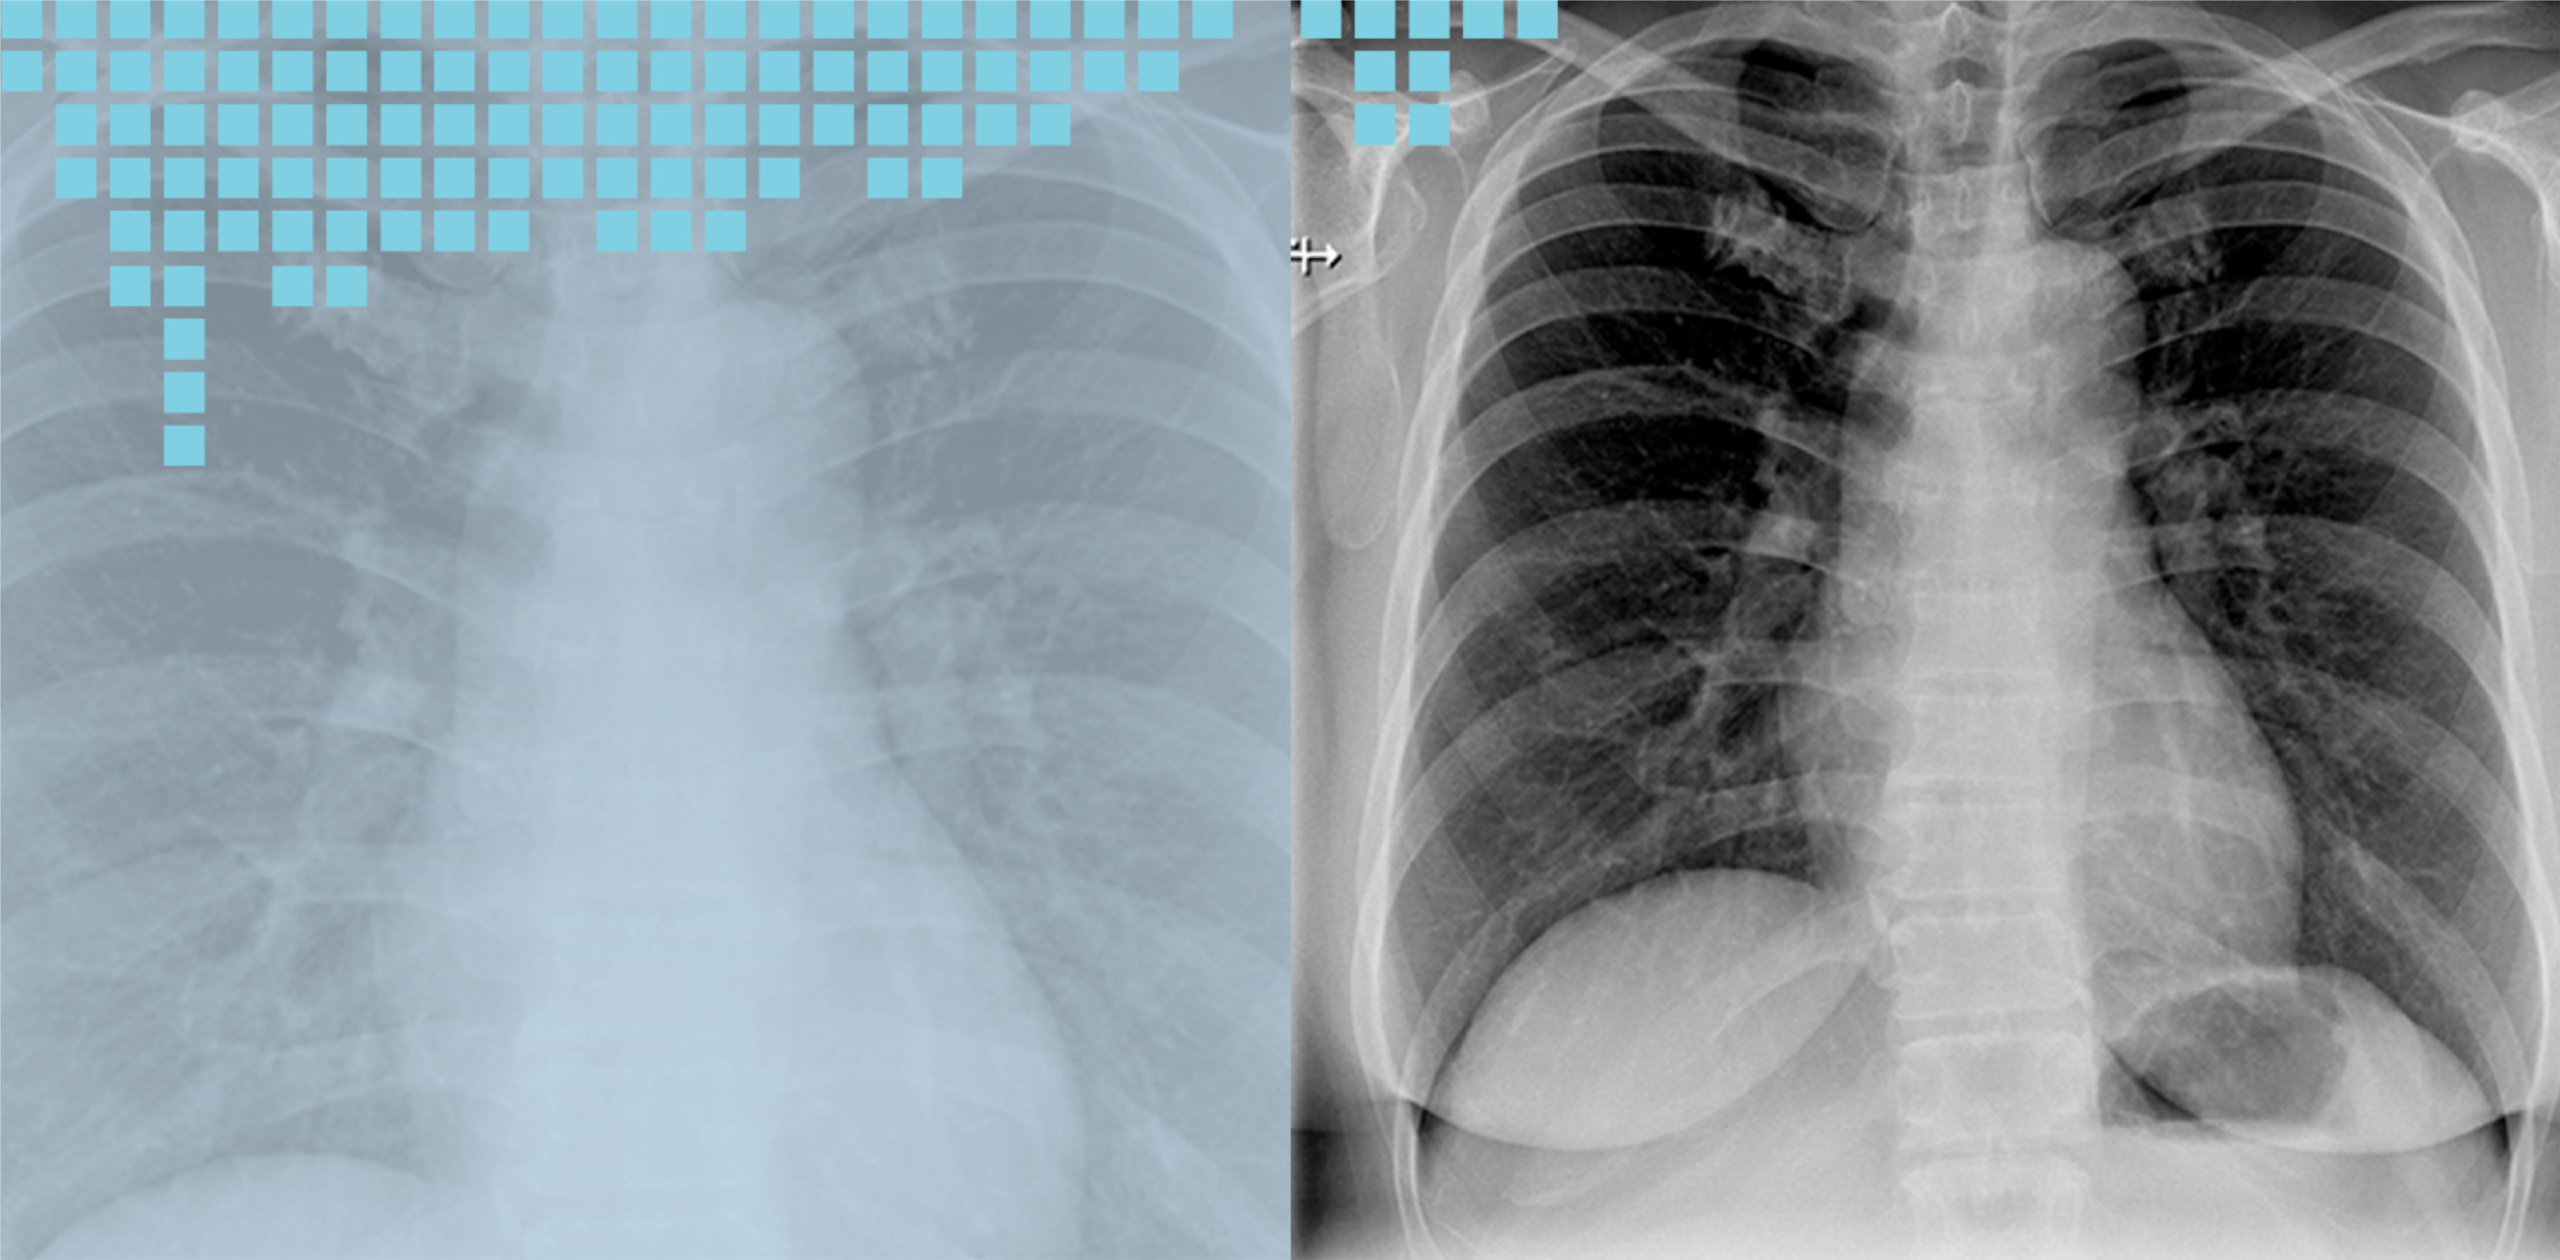

Our advanced digital radiography systems enhance productivity, patient comfort and workflow. Images produced can be transferred digitally throughout the hospital via network to improve patients’ turnaround time and throughput.

• Chest X-Ray